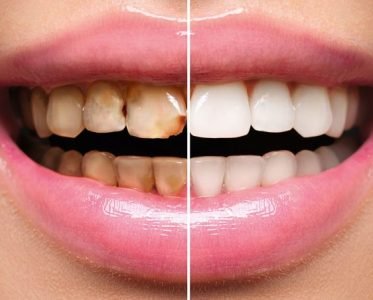

We hope you liked this article and it was a help for you in knowing about the treatment of overbite. If you are still in doubt about overbite treatment then visit our website where you’ll be able to find the results of overbite before and after that will help you understand its benefits.